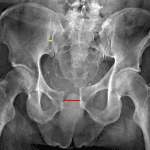

- Diastasis of the pubic symphysis measuring up to 3 cm

- Mild widening of the right sacroiliac joint

- Unstable pelvic ring injury (APC II)

Unstable pelvic ring injury with diastasis of the pubic symphysis measuring up to 3 cm and mild widening of the right sacroiliac joint.